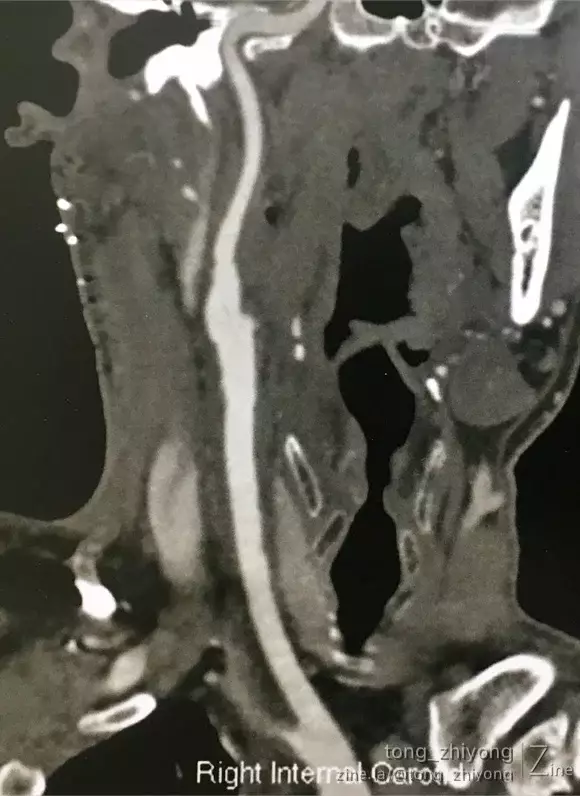

CTA可见:右侧颈动脉重度狭窄,动脉粥样硬化斑块破裂,造影剂进入斑块。